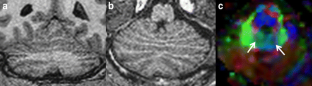

Diffusion tensor imaging (DTI) is an advanced MR technique that provides qualitative and quantitative information about the micro-architecture of white matter. DTI and its post-processing tool fiber tractography (FT) have been increasingly used in the last decade to investigate the microstructural neuroarchitecture of brain malformations. This article aims to review the use of DTI and FT in the evaluation of a variety of common, well-described brain malformations, in particular by pointing out the additional information that DTI and FT renders compared with conventional MR sequences. In addition, the relevant existing literature is summarized.